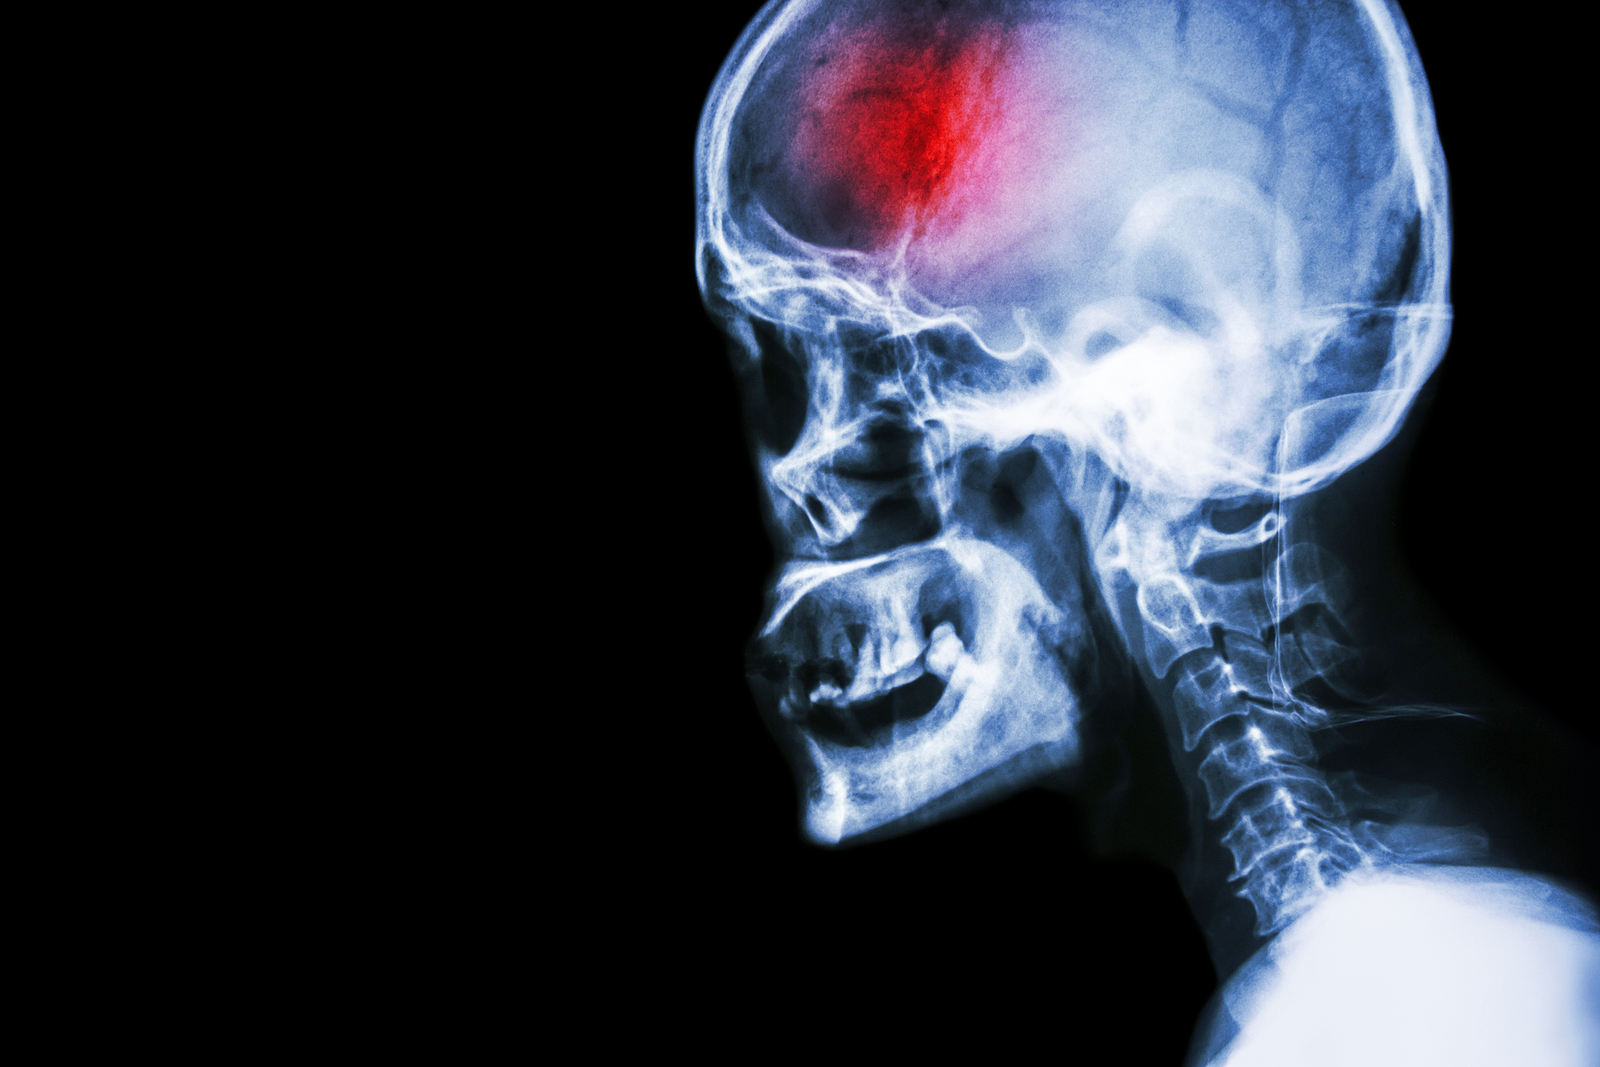

A stroke (previously known as a cerebrovascular accident) when there is a decreased flow of blood to the brain from either a blockage in the blood vessels that supply the brain (ischemic stroke), or a bleed from the blood vessels that supply the brain (hemorrhagic stroke). When the blood flow to the brain is blocked it prevents the brain from getting the needed oxygen and nutrients to function. Without oxygen the brain cells can be permanently damaged or die and the physical and mental functions related to that area of the brain will be affected. A stroke is a medical emergency and rapid treatment is crucial to decreasing the damage caused by a stroke.

- Hemorrhagic stroke: a stroke that is caused by a bleed that disturbs the blood flow to the brain and puts pressure on the surrounding tissue.

Computed Tomography (CT) scan and/or Magnetic Resonance Imaging (MRI) scan: These tests are done on your brain and used to locate the exact location of the stroke and to determine if it has been caused by a blockage or a bleed. These tests can also help rule out other conditions that may be causing symptoms, such as an infection or a brain tumour